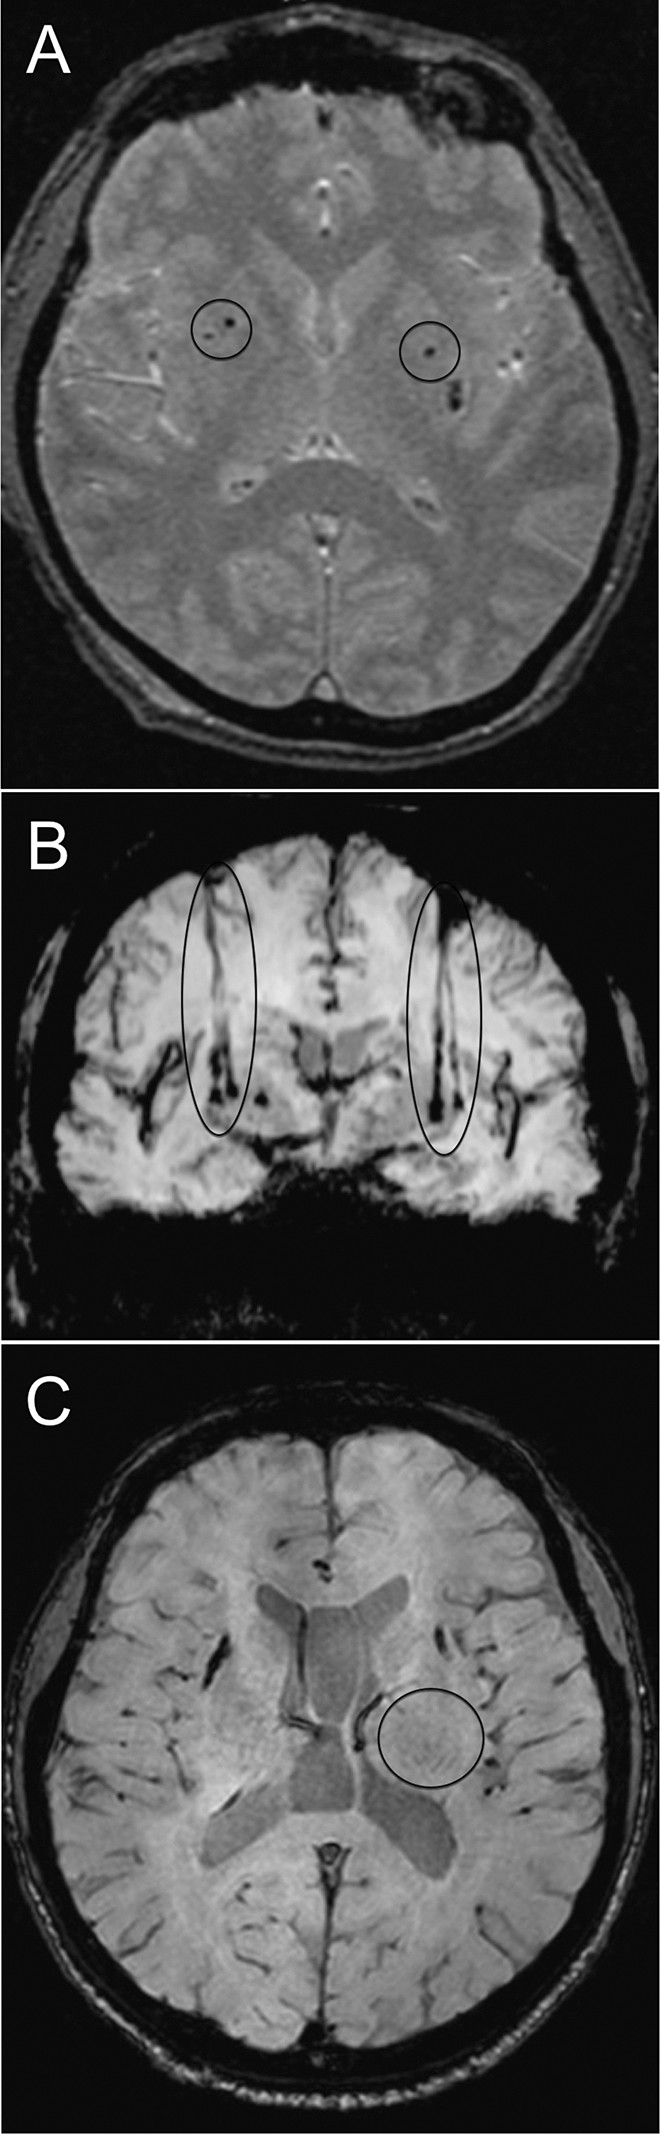

移植患者的代表性腦部 MR 圖像

如圖2所示。細胞植入的位點和軌跡路徑如圖 1 和 2 所示。分別參見圖 2A 和 2B。在1、2和4年隨訪的幾個針跡結束時,在 T2 加權圖像上識別出小簇低信號。在 P4 的年度 MRI 監測中,在右側殼核(圖2C)中觀察到強大的移植物生長,沒有大腦結構的異常。未顯示腫瘤形成的證據。